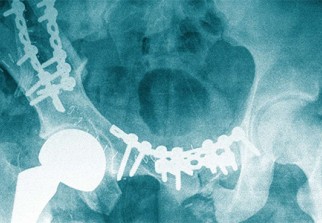

Cette enquête de grande ampleur, publiée par Le Monde et la cellule investigation de Radio France, partenaires du Consortium international des journalistes d'investigation (ICIJ), a mis en cause les pacemakers, les prothèses de hanches, les prothèses mammaires PIP (Poly Implant Prothèse) et les implants contraceptifs Essure (méthode de contraception définitive pour les femmes).

L'enquête révèle que le nombre total d’incidents est de l'ordre de 5 477 285, ce qui laisse indiquer qu'il s'agit, en dix ans, de plus de 82 000 morts, 1,7 million de blessés et 3,6 millions de défaillances, précise le consortium, auteur de l'enquête qui dit avoir bataillé "ferme" contre l’opacité des administrations de 36 pays pour "arracher des chiffres".

"Ces chiffres vertigineux, ce sont les dommages causés ces dix dernières années rien qu’aux Etats-Unis par les dispositifs médicaux, une famille d’outils de la médecine qui comprend les pompes à insuline, les pacemakers ou les prothèses de hanche", qui ne représentent qu'une "infime partie" de la réalité, précise-ton.